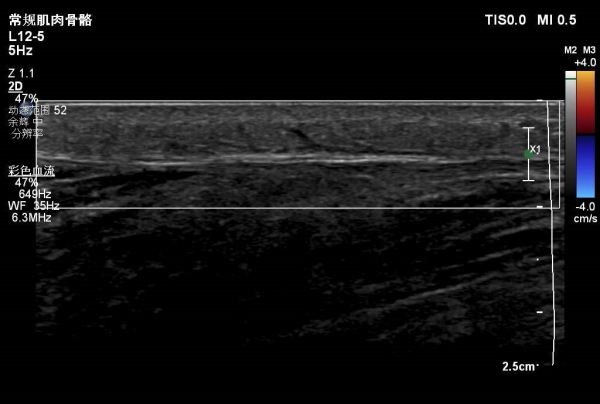

大腿包块—病例

患者大腿远端浅表可见一包块隆起,自述半月前出现红肿,目前未见明显红肿,触摸感觉微痛。

根据病情考虑可能蚊虫叮咬水肿。大家考虑是什么?有没有专家给看看,是什么?谢谢。